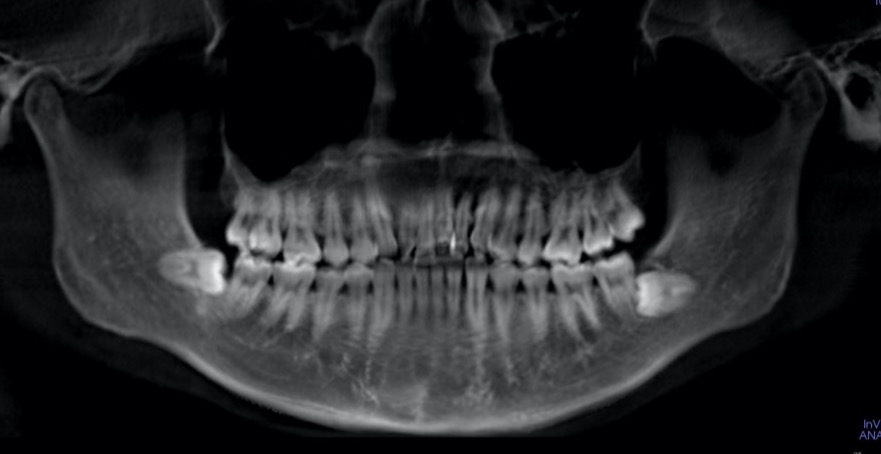

医院ブログ 2025/07/19【歯列矯正】被せ物がたくさん入っていても矯正治療はできる?